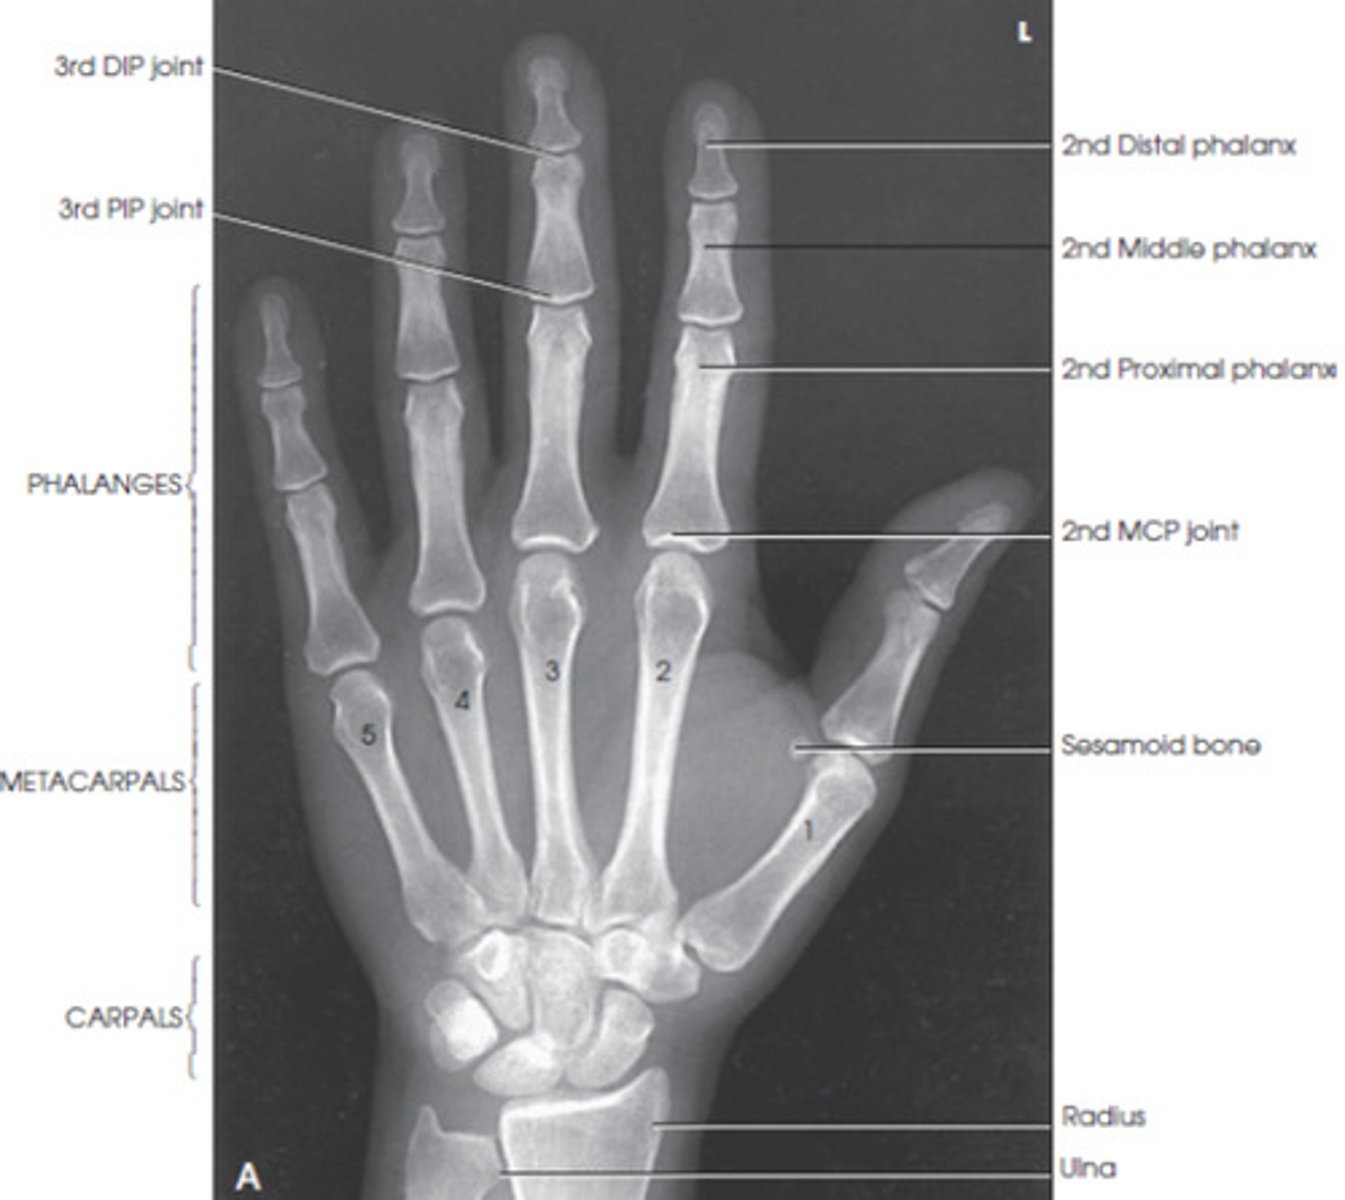

Anatomy and biomechanics of the hand Plastic Surgery Key Radius And Ulna Joint Type The radius pivots around the ulna to produce movement at the. The radius is a long bone in the forearm. The design of the radius and ulna as well as the joints between them enable pronation and supination of the forearm and hand. It lies laterally and parallel to ulna, the second of the forearm bones. The radius and the. Radius And Ulna Joint Type.